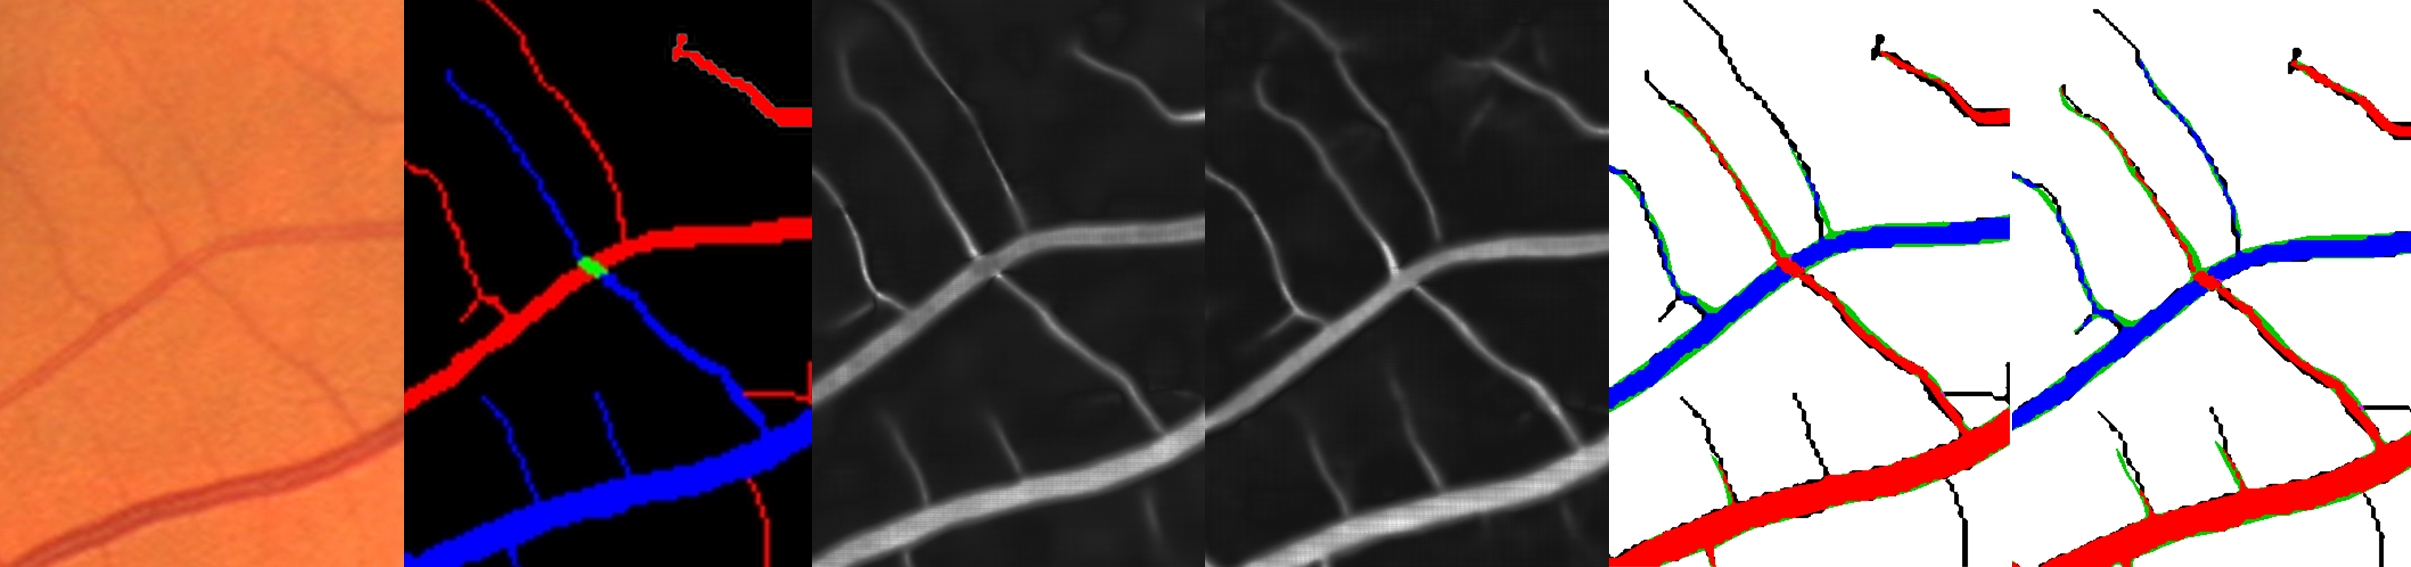

2.2.1 Extraction of Vessel Branches

The vessel segmentation contains all the pixels not labeled by the CNN as background (see Fig. 4 b)). This vessel segmentation is first skeletonized using Zhang-Suen method [45]. Then, the connected components of the vessel tree (see Fig. 4 c)) are obtained with the classical two-pass algorithm after removing bifurcations and crossings. The bifurcations and crossings are identified with hit-and-miss morphological operations. The set of pixels belonging to a given connected component forms a branch, called . The two endpoints and of each branch and the orientations and at these points are calculated and will be used for the graph representation.

2.2.2 Graph Representation

The retinal vasculature is represented mathematically as a connected, undirected graph with a cost function . The nodes of this graph are the vessel branches . Each node is associated to the branch’s likelihood of being an artery, . This branch score is calculated from the pixel scores previously obtained from the CNN classification and re-centered around zero:

| (4) |

The weight associated to each edge of the graph expresses the cost of linking two graph nodes (i.e. vessel branches). If the cost is low, it means the likelihood is high that two branches and are connected in the retinal vascular tree. This cost is defined as the sum of a position cost and a label cost . The weight of the label cost relative to the position cost is controlled by two parameters and . The position cost is defined as the minimal distance between the two endpoints of each branch to which we add an extra cost on angles in order to favor the connection of collinear branches. The label cost is equal to the difference between the two branches’ scores and :

| (5) |

| (6) |

2.2.3 Score Propagation in the Minimum Spanning Tree

The idea is to propagate the scores from one node to another according to the cost of the edge connecting those two nodes. If the cost is low, then the propagation should be greater, and vice-versa. To implement this process, each node receives a likelihood score from another node . This score received by is exponentially attenuated by the position cost between the two nodes. But instead of calculating, for a given node , the likelihood scores from all attenuated by the costs , an efficient method of score aggregation used for stereo correspondence [46] is adapted for our application. The graph is first simplified into its minimum spanning tree, obtained with the Prim algorithm [47] (see Fig. 4 d) for an example). In this minimum spanning tree, the sum of the costs along the path connecting two nodes should be a good approximation of the total cost between these two nodes in the original graph. The tree is then traversed in post-order from the leaves up to the root, and each initial score is updated to an intermediate score denoted . To do this, each parent receives from its children their intermediate scores exponentially attenuated by the position costs , and these are added to the parent’s current score. We use the following notation meaning that the parent of node is . The intermediate scores of the leaves are simply their initial scores, since they have no children. The amount of attenuation for a specific cost is controlled by :

| (7) |

The remaining likelihood scores to propagate are those coming from sibling nodes. Since upward propagation has already occurred, it is possible to calculate the remaining propagation coming from the siblings. The tree must now be traversed in pre-order from the root down to the leaves. The intermediate scores are updated to the final scores . For the root, as it has no parent, the final score is simply equal to its intermediate score. Each parent then transmits to each of its children the likelihood scores (that now contain the aggregation of scores from all subtrees) minus the likelihood score already sent by that child, resulting in the final score for each child (see the resulting tree in Fig. 4 e):

| (8) |

This entire procedure is repeated until convergence or for a sufficient number of iterations. This allows some nodes to be reconnected properly in the minimum spanning tree so that they can receive the appropriate score propagation (for example the node b in Fig. 4 f)). Experimentally, we found that two iterations were usually sufficient to reach convergence.

Finally, the labeling of the vessel segmentation is updated according to the branches’ final scores . The branch is labeled as a vein if is negative and as an artery if is positive (see Fig. 4 g)).